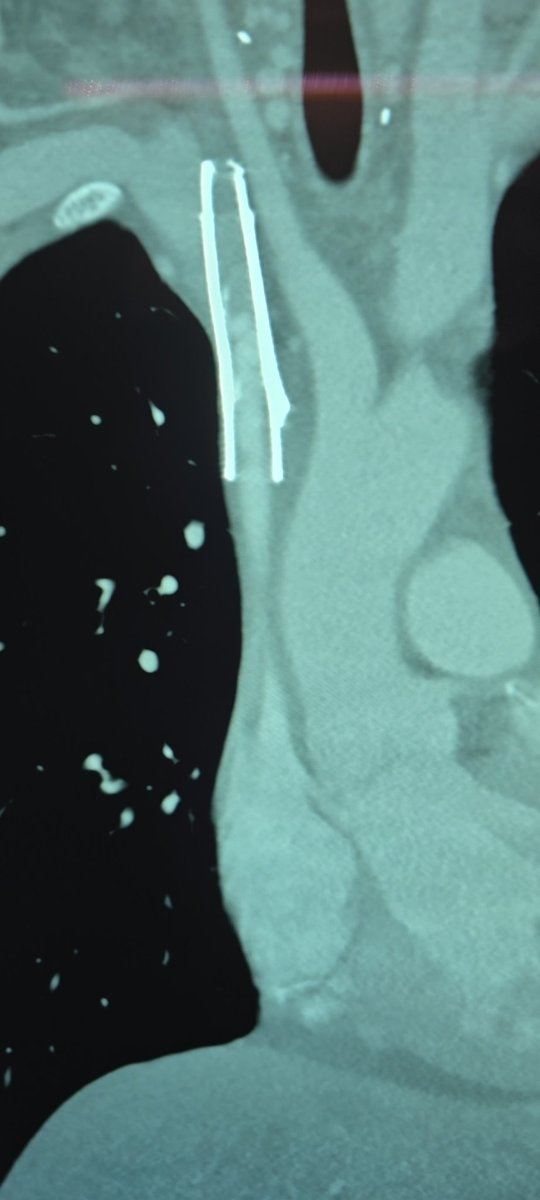

What better way to start holiday weekend call than a TIPS PR

Bleeding tips:

22 mins from lido to pressure, single stick w/ #ScorpionX

Gradient 27>8mmHg, 8cm Viatorr

#ICETIPS @WLGore @ArgonMedical

Props again to @tarheeldylan and @_backtable (episode 455 for basic technique)